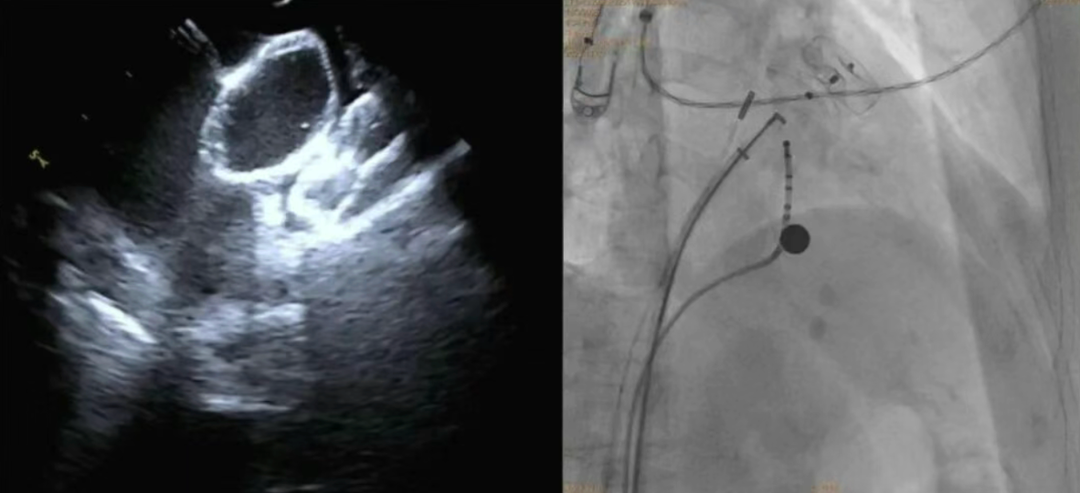

大众卫生报·新湖南客户端11月30日讯(通讯员 杨帅 陈纯)近日,岳阳市中医医院心血管病科成功为一名76岁房颤合并脑卒中患者,实施首例心腔内超声(ICE)引导下“房颤射频消融+左心耳封堵”一站式手术。该手术实现了精准治疗,有效降低了患者卒中复发与长期服药风险。

手术在导管室、麻醉科、超声科等多科室协作下进行。团队经股静脉穿刺,在三维标测系统引导下完成房颤射频消融,随后在X线及心腔内超声指导下植入左心耳封堵伞,成功闭合左心耳开口。整台手术历时约两小时,患者房颤转复为正常窦性心律,术后恢复良好,胸闷、心悸症状明显改善。